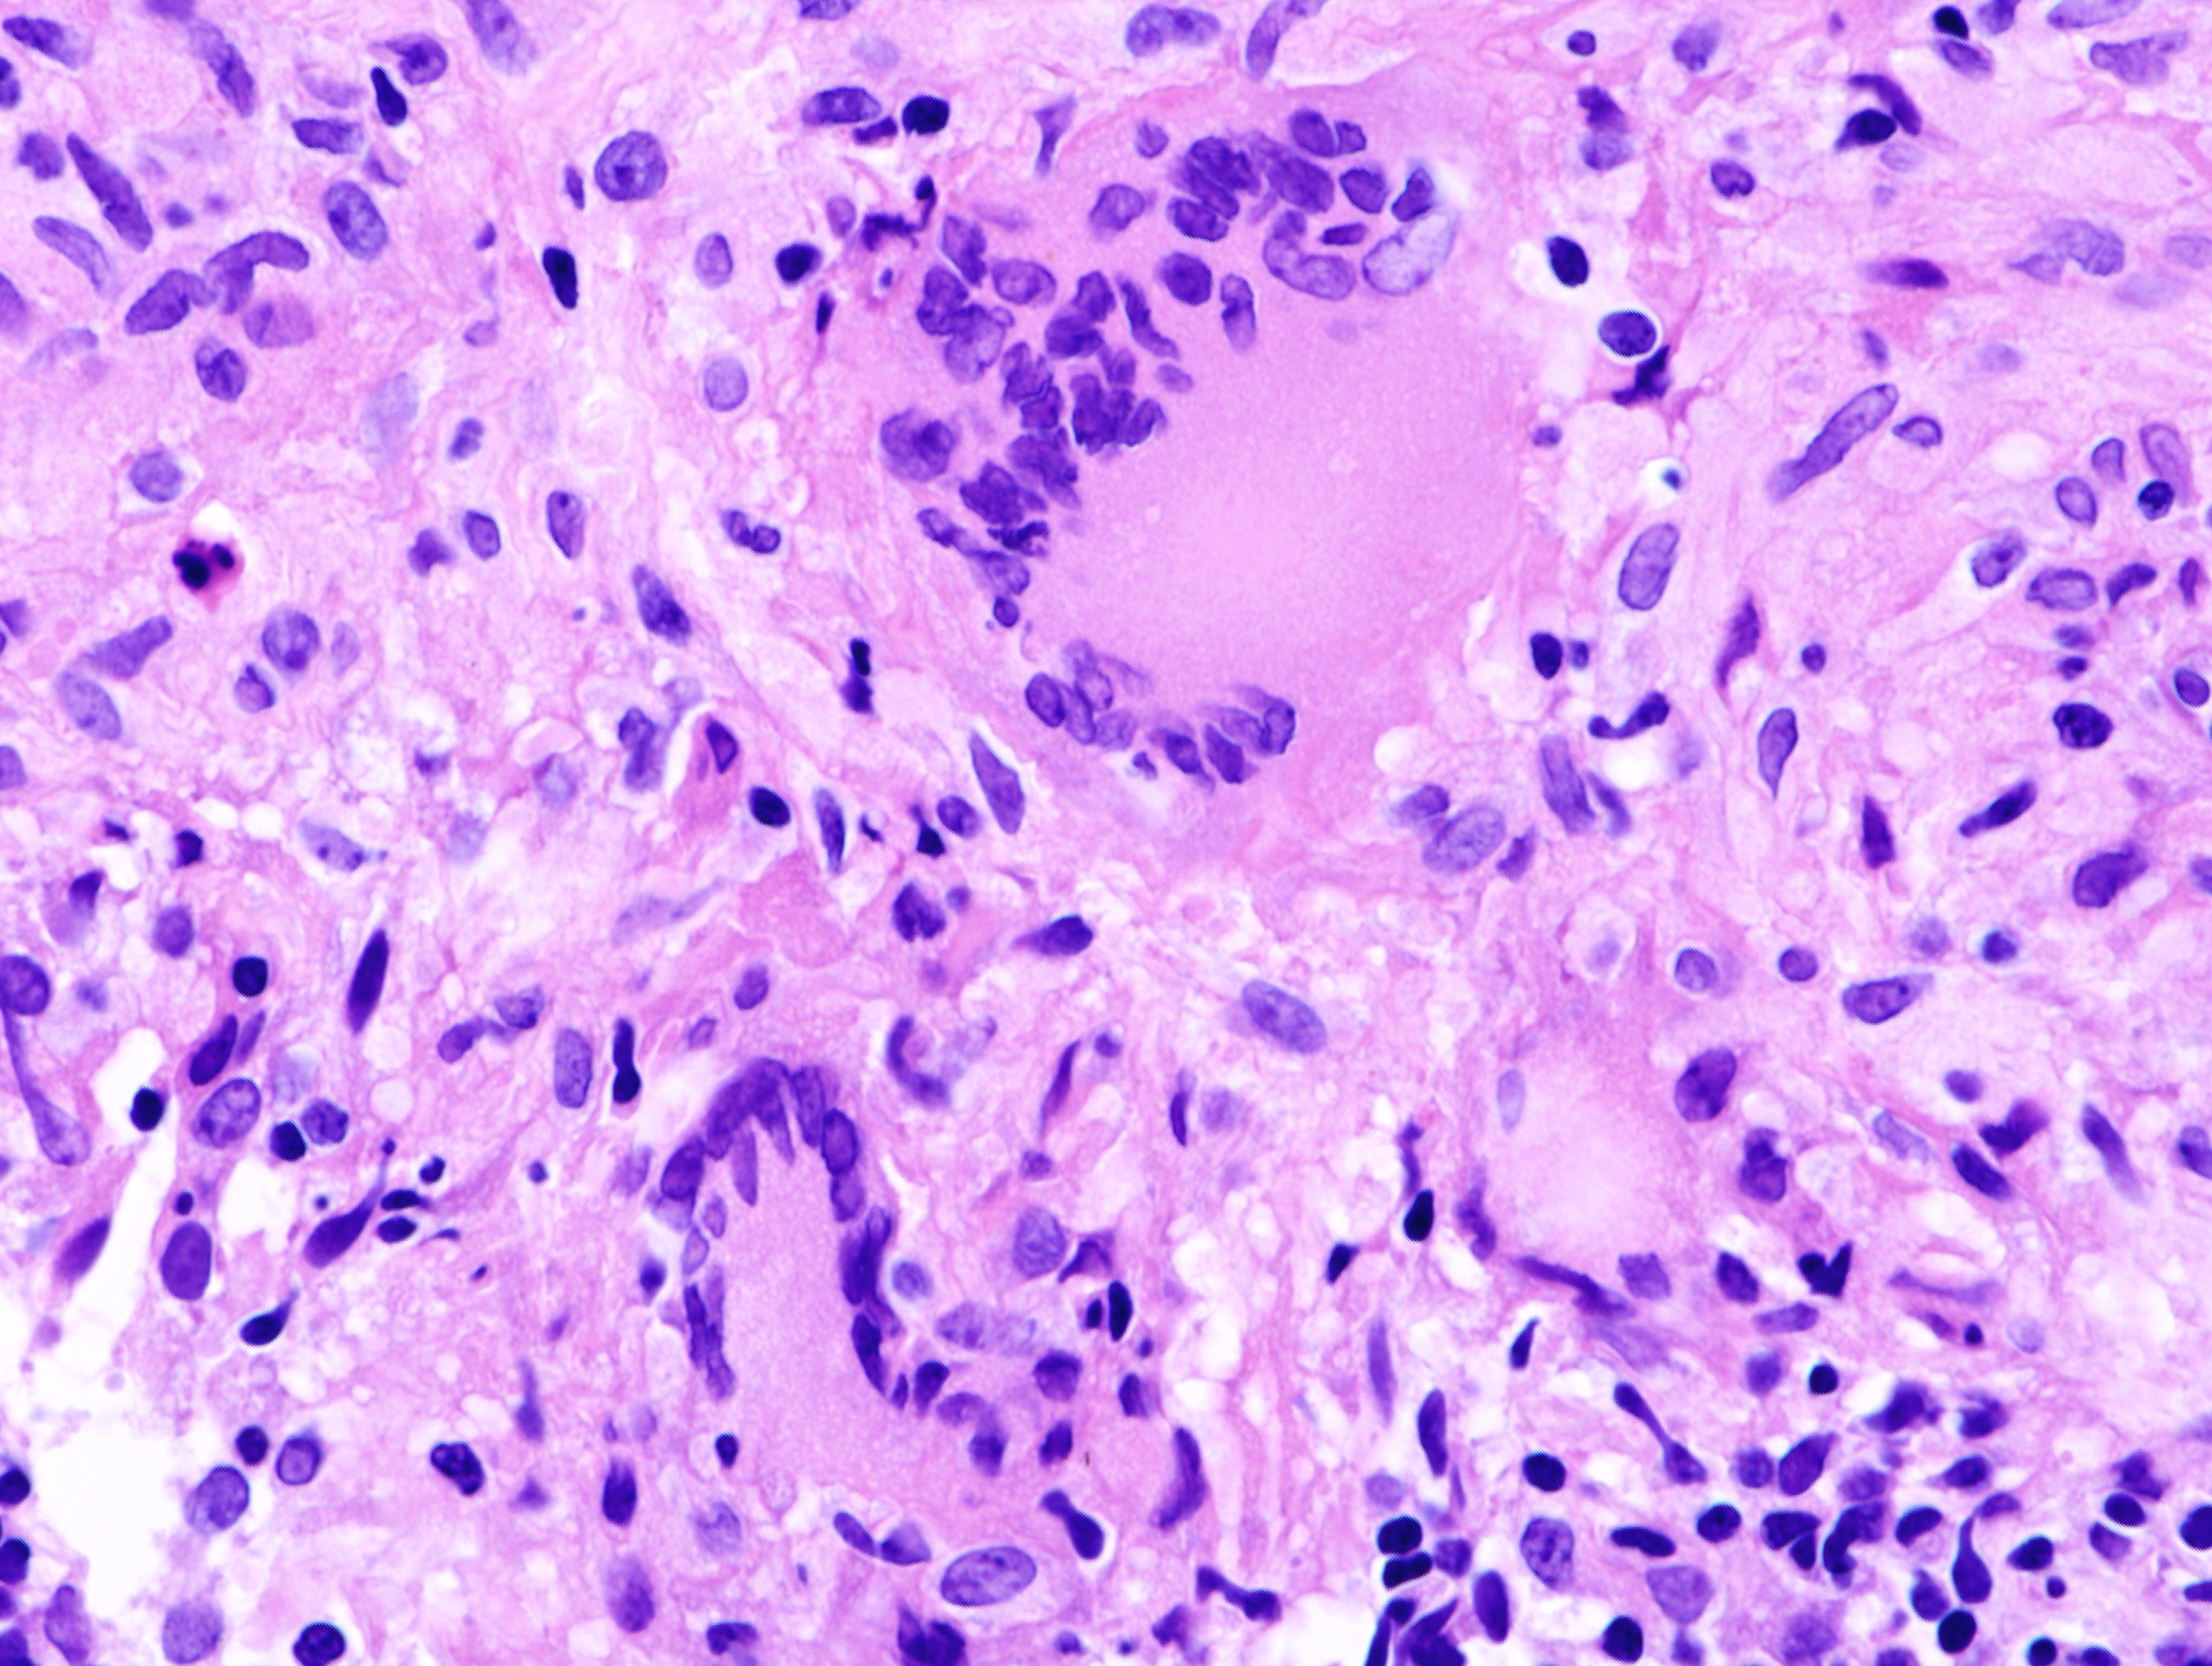

Mikroskopisches Bild eines tuberkulösen Granuloms. Aufgrund der Färbetechnik sind hierauf keine Mykobakterien zu erkennen.

Foto: KGH Permission

Lizenz: GFDL